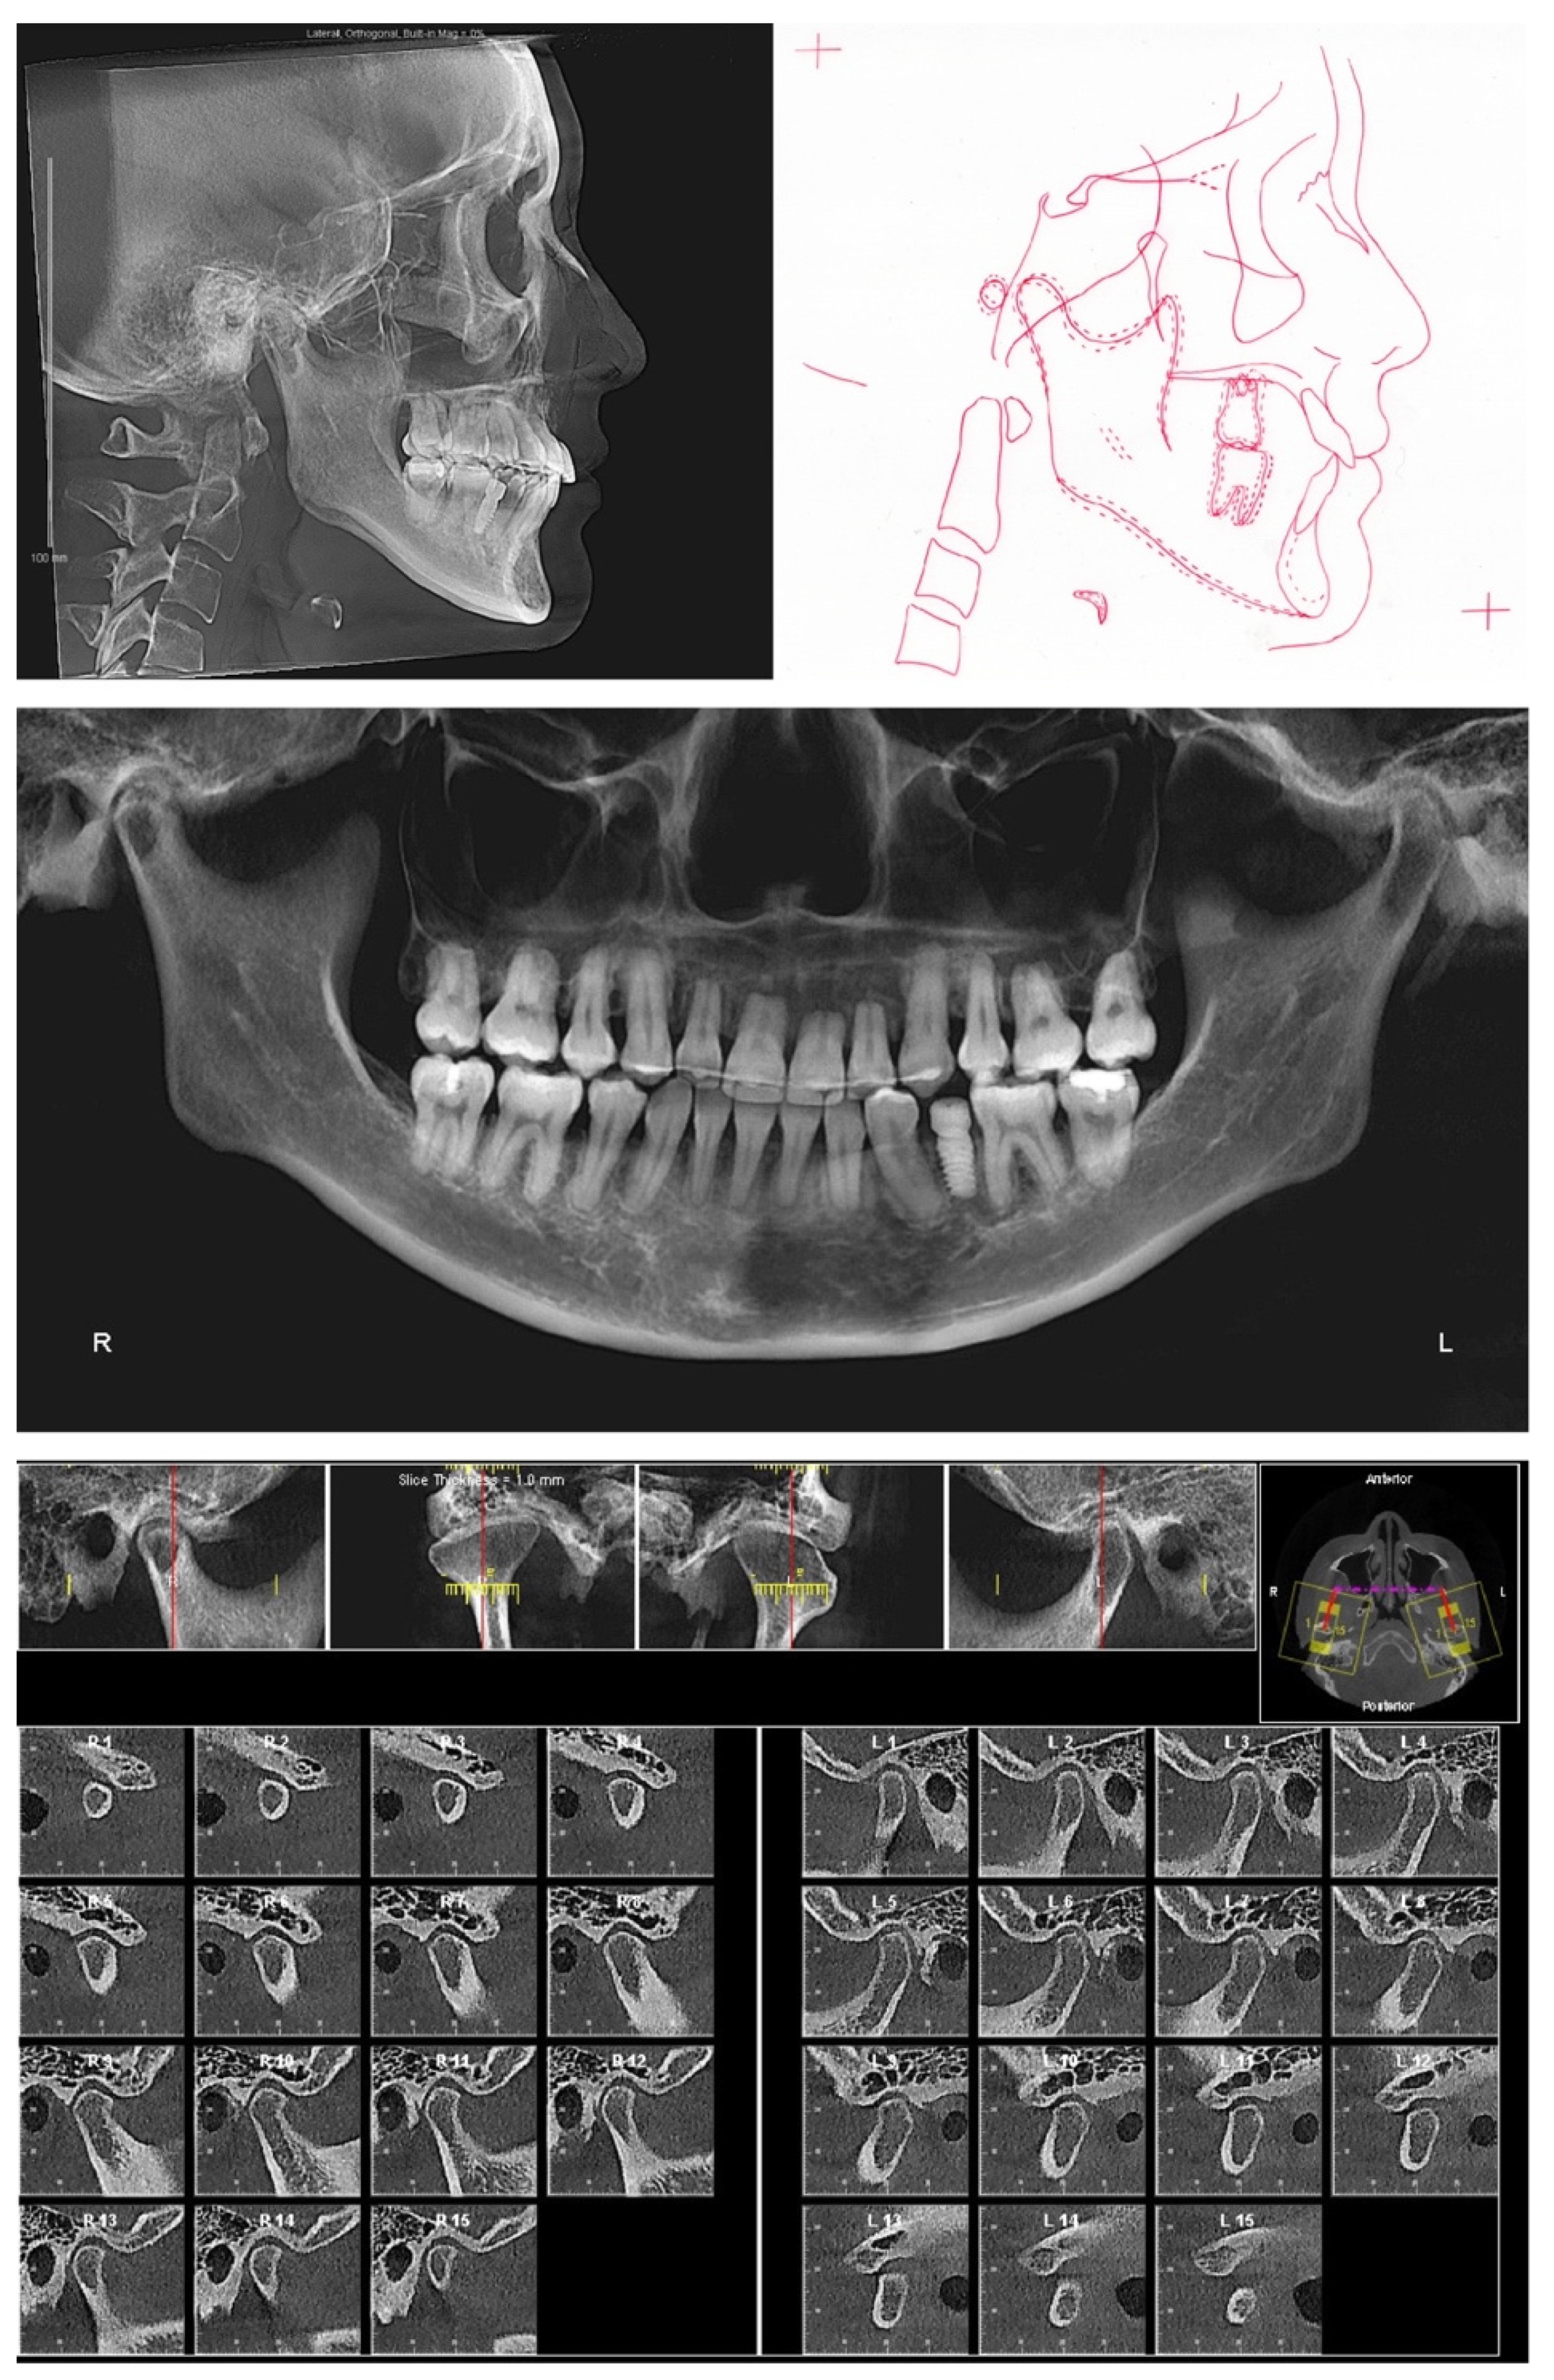

At the completion of treatment, the severe proclination and protrusion of maxillary anterior teeth were corrected, and acceptable overbite and overjet were established (Figure 9 and Figure 10). The temporomandibular joint spaces were similar on both sides, indicating a CR occlusion was established (Figure 10), and the patient didn’t report any joint discomfort during and at the end of the treatment. The intact cortical layers of the condylar heads were also maintained (Figure 10). The cross-section slices of the maxillary anterior teeth further proved the correction of the inclination of the anterior teeth and a better position of the tooth roots in relation to the alveolar ridge (Figure 11). When comparing the root length of maxillary anterior teeth, minimum root resorption (within 1 mm) was observed during the whole treatment (Table 2).

Pre- and post-treatment superimposition (Figure 12, Table 1) demonstrated the maxillary and mandibular molar distalization and anterior teeth retraction and retroclination. In detail, the maxillary central incisors were retracted 7.9 mm and retroclined 33 degrees (Figure 12A,B), the maxillary left molars were distalized 8 mm, the maxillary right molars were distalized 4 mm (Figure 12C), the mandibular left molars were distalized 5 mm, and the mandibular right molars were distalized 2 mm (Figure 12E). It is worthy to note that the molar distalization in this case has reached its anatomic limitation, as in the post-treatment panoramic X-ray (Figure 10), a limited amount of maxillary tuberosity was left distal to the maxillary left second molar, and the mandibular left second molar was position close to the retromolar fossa.

Figure 10. Posttreatment radiographs and cephalometric tracing.

Figure 11. Posttreatment cross section images of maxillary anterior teeth. Maxillary right canine: slices #3–#7. Maxillary right lateral incisor: slices #8–#12. Maxillary right central incisor: slices #13–#17. Maxillary left central incisor: slice #18–#23. Maxillary left lateral incisor: #24–#28. Maxillary left canine: #29–#33.